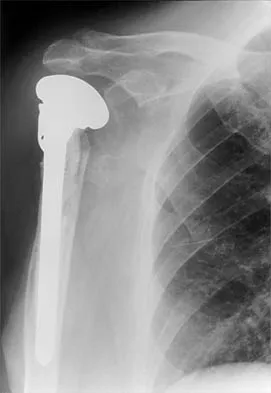

Figure 36a shows the current radiograph of a 65-year-old woman who slipped and fell. History reveals that prior to the fall she was actively functioning without pain. Figure 36b shows a radiograph obtained 1 year ago. Based on the fracture pattern, the failure is most likely related to

The radiograph shows a fracture distal to the prosthesis in a stable, apparently well-fixed prosthetic stem. The well-fixed prosthesis-bone composite is stiff, creating a modulus mismatch between the proximal and distal femur. Therefore, the risk of fracture, particularly in osteoporotic bone, is increased at this level. Revision of the stem to a longer construct is unnecessary, and standard plate and screw fixation has been shown to yield union rates of greater than 90%. Nonsurgical treatment of fractures distal to the tip of the prosthesis results in high nonunion rates, reported to be from 25% to 42%. Johansson JE, McBroom R, Barrington TW, Hunter GA: Fracture of the ipsilateral femur in patients with total hip replacement. J Bone Joint Surg Am 1981;63:1435-1442. Bethea JS III, DeAndrade JR, Fleming LL, Lindenbaum SD, Welch RB: Proximal femoral fractures following total hip arthroplasty. Clin Orthop 1982;170:95-106.